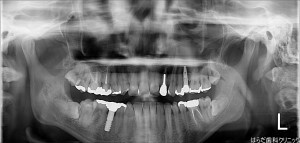

【左上2目】インプラント1本埋入 GBR

今回はGBRの状態でインプラントも同時に埋入するかを確認しながらのオペでした。

問題がなかったので、インプラントの埋入も同時に行う事が出来ました。